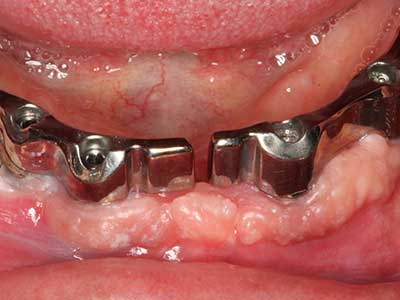

La piezochirurgia presenta altri vantaggi per quanto riguarda la raccolta di blocchi ossei. Oltre all'elevata precisione dell'osteotomia appena descritta, l'utilizzo di puntine per sega molto sottili permette di minimizzare in maniera significativa la perdita di materiale. È molto probabile che si verifichi una maggiore perdita di materiale durante la raccolta utilizzando puntine di strumenti più spessi, in particolare delle frese Lindemann (Lakshmiganthan, Gokulanathan et al. 2012). La separazione basale, necessaria in particolare per i trapianti di blocchi nella zona retromolare, viene semplificata grazie a seghe specificatamente progettate di forma rettangolare; di conseguenza la piezochirurgia è considerata una procedura precisa, semplice e sicura per la raccolta di blocchi di osso nella zona retromolare (Happe 2007) (figg. 1-12).